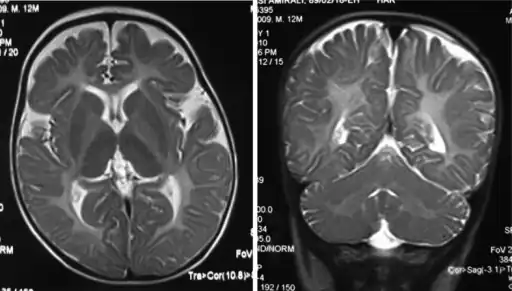

The diagnosis of Pelizaeus–Merzbacher disease is often first suggested after identification by magnetic resonance imaging of abnormal white matter (high T2 signal intensity, i.e. T2 lengthening) throughout the brain, which is typically evident by about 1 year of age, but more subtle abnormalities should be evident during infancy.

Iso intensity in bilateral periventricular deep white matter Left- MRI,abnormal high signal internal capsule,Right MRI,high signal white matter of cerebellum

Left- MRI,abnormal high signal internal capsule,Right MRI,high signal white matter of cerebellum